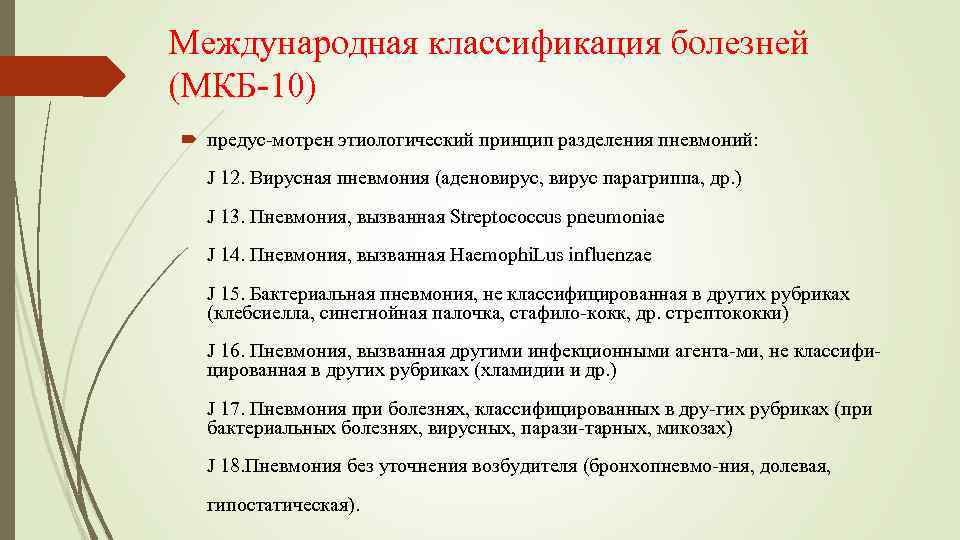

Международная классификация болезней (МКБ 10) предус мотрен этиологический принцип разделения пневмоний: J 12. Вирусная пневмония (аденовирус, вирус парагриппа, др. ) J 13. Пневмония, вызванная Streptococcus pneumoniae J 14. Пневмония, вызванная Haemophi. Lus influenzae J 15. Бактериальная пневмония, не классифицированная в других рубриках (клебсиелла, синегнойная палочка, стафило кокк, др. стрептококки) J 16. Пневмония, вызванная другими инфекционными агента ми, не классифи цированная в других рубриках (хламидии и др. ) J 17. Пневмония при болезнях, классифицированных в дру гих рубриках (при бактериальных болезнях, вирусных, парази тарных, микозах) J 18. Пневмония без уточнения возбудителя (бронхопневмо ния, долевая, гипостатическая).

Международная классификация болезней (МКБ 10) предус мотрен этиологический принцип разделения пневмоний: J 12. Вирусная пневмония (аденовирус, вирус парагриппа, др. ) J 13. Пневмония, вызванная Streptococcus pneumoniae J 14. Пневмония, вызванная Haemophi. Lus influenzae J 15. Бактериальная пневмония, не классифицированная в других рубриках (клебсиелла, синегнойная палочка, стафило кокк, др. стрептококки) J 16. Пневмония, вызванная другими инфекционными агента ми, не классифи цированная в других рубриках (хламидии и др. ) J 17. Пневмония при болезнях, классифицированных в дру гих рубриках (при бактериальных болезнях, вирусных, парази тарных, микозах) J 18. Пневмония без уточнения возбудителя (бронхопневмо ния, долевая, гипостатическая).